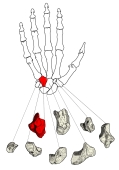

・有頭骨は手根骨の1つで、遠位手根骨の中で最も内側(小指側)に位置する。

・イラストや写真を掲載しているサイトⅠ(左手・手背面のCG) ・イラストや写真を掲載しているサイトⅡ(2方向からの単体のイラスト) ・イラストや写真を掲載しているサイトⅢ(筋の付着が分かるイラスト) ・イラストや写真を掲載しているサイトⅣ(手根骨周辺の断面、赤は有頭骨) ・イラストや写真を掲載しているサイトⅤ(レントゲン画像、手根骨周辺) ・イラストや写真を掲載しているサイトⅥ(レントゲン画像、前腕下部~中手骨)